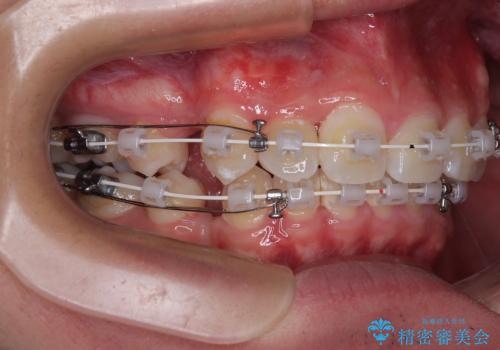

抜歯矯正で叢生と正中のずれを改善|審美装置による矯正症例

- 今回ご紹介するのは、

「全体的なデコボコ(叢生)」「上下の正中のずれ」 を主訴として来院された20代男性の患者様の症例です。

叢生が強く、歯が並ぶスペースが不足していたため、

上下左右の第一小臼歯を抜歯して、矯正治療のための適切なスペースを確保する計画としました。